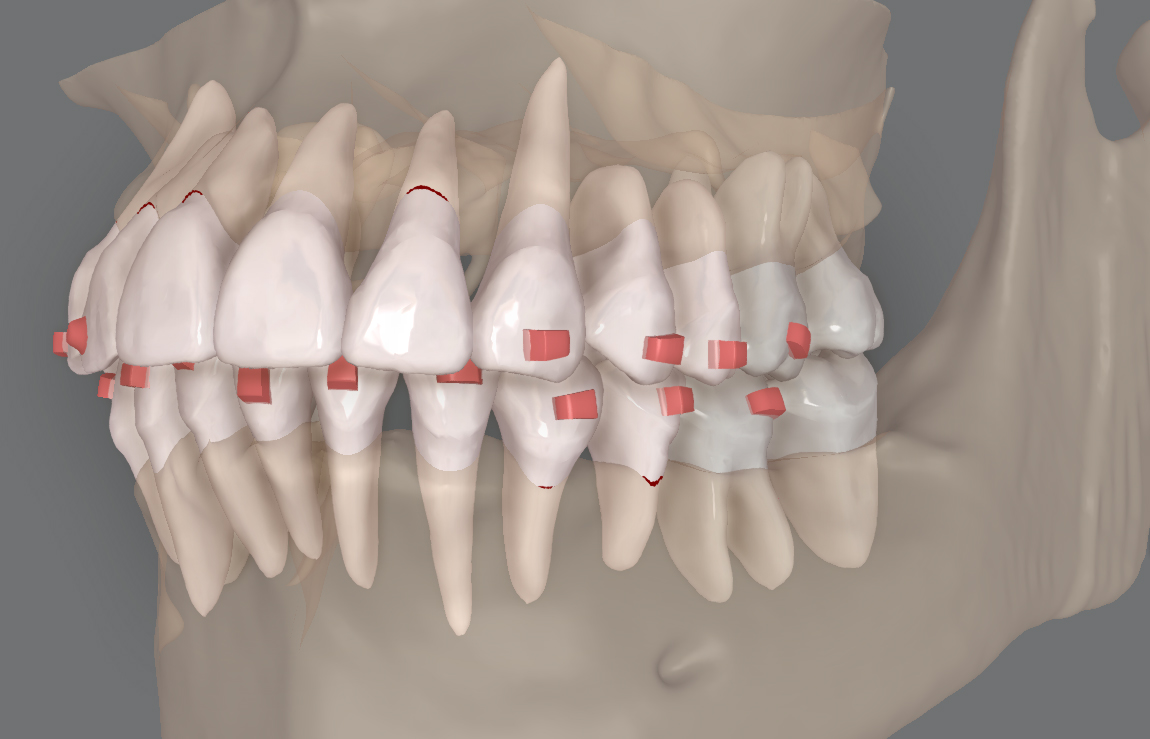

インビザライン治療においては、広く知られるようになりましたが『クリンチェック』というシミュレーションソフトを利用いたします。

患者様の現在の歯並びがモニター上にスタート地点として再現され、ゴールとする理想の歯並びへと歯の移動を計画していくのですが、このクリンチェックシミュレーションソフトには、歯の根っこの形状や位置関係の情報、上下の顎の骨の厚みなどの情報、マウスピースによる矯正力にどの程度、反応するのかとった情報などが抜けております。これらの情報を勘案しながら、治療計画を立案し、計画通りに歯を移動させていかなければなりません。

当院で使用しているインビザラインのシミュレーションソフト「クリンチェック」上で、1歯1歯のミリ単位での移動を視覚化しております。計画通りに歯が動いているか?計測しながら治療を進めてまいります。

歯科用CTとシミュレーションソフトを連携させ、顎の骨から飛び出さないような安全な位置に歯の移動を行ってまいります。

あまりご存じで無いかもしれませんが、インビザライン治療に際して使用される「クリンチェックシミュレーション」による治療計画は、口腔内スキャナー(i-Tero)による現在の患者様の歯並びデータをインビザライン社に送付すると、インビザライン社の社内オペレーターがまず、初期的に歯列の移動計画をつくり、クリニックにデータ返信してきます。

このデータを『承認』すると、マウスピースが出来上がってくるのですが、この初期的な移動計画の精度はあまり高くないため、ドクターが独自のノウハウに基づき、初期データに手を加えることで歯の移動の実現性を高めていく必要があります。

当院においては、初期データをそのまま承認することはせず、計画を再考しながら、この治療計画を仕上げ、マウスピース製作に進むようしております。

インビザライン社による初期

当院であらたに仕上げた